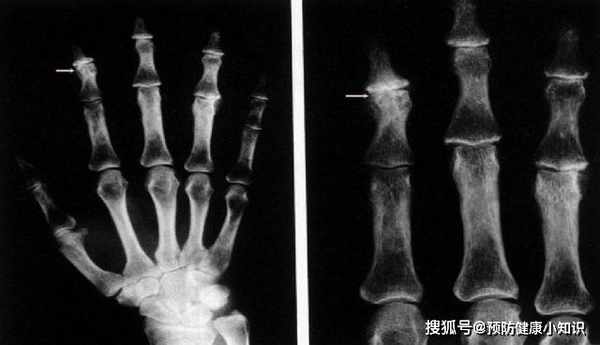

(1)X線平片骨關節

發現骨質疏鬆症、骨關節炎或骨軟化等,多見於手術。